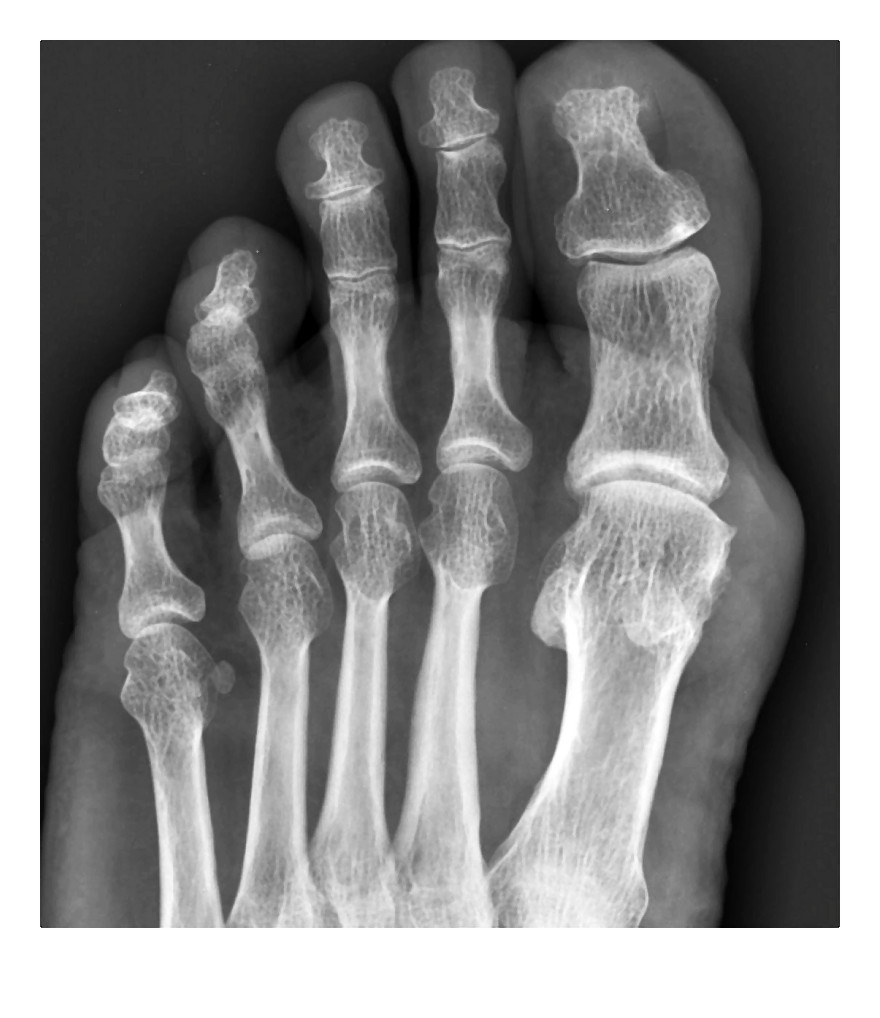

4. Badania biochemiczne wątrobyWątroba osób spożywających zbyt dużo tłuszczu lub nadużywających alkoholu może ulegać uszkodzeniu. W ocenie stanu komórek wątroby (hepatocytów) pomocne jest ustalenie aktywności tzw. enzymów wątrobowych. W wyniku uszkodzenia hepatocytów (przy niedotlenieniu lub pod wpływem działania toksyn lub wirusów) wzrasta aktywność enzymów wątrobowych uwalnianych z hepatocytów do krwi. Badanie stopnia uszkodzenia komórek wątrobowych polega na zmierzeniu we krwi aktywności ALT (Alat, aminotransferazy alaninowej), AST (Aspat, aminotransferazy asparaginianowej), ALP (fosfatazy zasadowej, inaczej alkalicznej), BIL (Bilirubiny całkowitej) i GGTP (Gamma-glutamylotransferazy). Badania te są objęte historyczną nazwą próby wątrobowe i, gdy są wykonywane łącznie, badany powinien być na czczo. Kolejne fazy uszkodzenia wątroby mogą prowadzić do włóknienia wątroby i w konsekwencji do marskości wątroby. Diagnostyka dysponuje badaniami biochemicznymi, które pozwalają na nieinwazyjną ocenę stopnia włóknienia wątroby i stopnia aktywności martwiczo-zapalnej o podłożu wirusowym (HCV, HBV). Panel badań przydatnych w diagnostyce tych schorzeń to FibroTest i FibroMax. Fibromax dodatkowo ocenia stopień stłuszczenia wątroby i stopień aktywności martwiczo-zapalnej o podłożu metabolicznym i alkoholowym. Wyniki badań mogą być wskazaniem do wykonania biopsji wątroby będącej badaniem rozstrzygającym. 5. Inne badania istotne w diagnostyce i monitorowaniu leczenia cukrzycy to pomiar:- stężenia insuliny - badanie zalecane w celu oceny ryzyka miażdżycy, chorób niedokrwiennych serca i nadciśnienia- peptydu C - odzwierciedla rzeczywistą ilość insuliny wytwarzanej w organizmie- glikowanej hemoglobiny (HbA1c) - odzwierciedla stężenie glukozy w okresie 3-4 miesięcy poprzedzającym badanie, jest retrospektywnym wskaźnikiem glikemii oraz wskaźnikiem rozwoju przewlekłych powikłań cukrzycy- fruktozaminy - wykonywany w przypadku chorych na niestabilną cukrzycę- ciał ketonowych w moczu - stosowany szczególnie w monitorowaniu leczenia cukrzycy typu 1- albuminy w moczu - pozwala na wykrycie minimalnych ilości białka wydalanego z moczem, co jest pierwszym sygnałem uszkodzenia nerek w przebiegu cukrzycy.Dna moczanowaJest chorobą, w przebiegu której dochodzi do nieprawidłowego ciągu przemian metabolicznych zasad purynowych, których końcowym produktem przemiany jest kwas moczowy. Kiedyś była postrzegana jako choroba ludzi bogatych i kojarzona z bogatą w mięso, alkohol i tłuszcze dietą. Objawia się nawrotowym zapaleniem i napadami bólu w stawach, głównie śródręczno-paliczkowym palucha, skokowym czy kolanowym.Objawy są spowodowane wytrącaniem się kwasu moczowego w stawach i strukturach okołostawowych wtedy, gdy we krwi następuje podwyższenie poziomu kwasu. Napady bólu, które trwają od kilkunastu dni do kilku tygodni, najczęściej wywoływane są przez wysiłek fizyczny, alkohol, uraz, niektóre leki oraz zabiegi operacyjne. Kilka lat po pierwszym napadzie rozwija się przewlekłe, wielostawowe zapalenie, w którym w okolicy stawów powstają złogi moczanów tzw. guzki dnawe.Nadmierny wzrost stężenia kwasu moczowego (hiperurykemia) może mieć charakter pierwotny (rozwija się w wyniku wrodzonych defektów metabolizmu) lub wtórny, który jest konsekwencją m.in. zwiększonej podaży niektórych produktów w diecie. Powikłaniami hiperurykemi może być dna moczanowa i uszkodzenie nerek. Profilaktyka dny opiera się na unikaniu produktów bogatych w puryny, podrobów (wątróbka), zup gotowanych na mięsnych wywarach czy warzyw strączkowych (groch, soczewica). Warto ograniczyć również picie herbaty i kawy, które mają działanie moczopędne. Nie należy zakwaszać organizmu słodyczami, tłustymi wyrobami czy napojami typu cola. Osobom otyłym w walce z dną pomoże pozbycie się zbędnych kilogramów. W tej sytuacji nie warto jednak działać na własną rękę, gdyż źle dobrany wysiłek fizyczny i dieta mogą pogorszyć stan chorego. Dlatego warto odchudzać się pod okiem reumatologa i dietetyka.